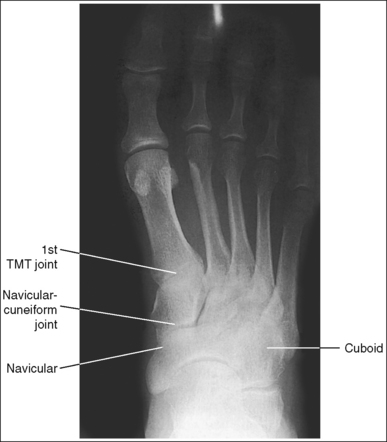

See Figures 6-17 and 6-18 and Box 6-6.

FIGURE 6-17 AP oblique foot projection with accurate positioning in a patient with a high longitudinal arch.

The foot demonstrates adequate obliquity. The cuboid-cuneiform joint space is open, the first and second intermetatarsal joints are closed, but the second through fifth intermetatarsal joint spaces are open, and the tarsi sinus and fifth metatarsal tuberosity are well demonstrated.

• To obtain an AP oblique foot projection, begin with the patient in a supine position with the knee flexed until the plantar foot surface rests against the receptor. Medially rotate the patient's leg and foot until the foot forms a 30- to 60-degree angle with the IR (Figure 6-19).

• Determining required obliquity. To determine whether a 30- or 60-degree rotation is needed, view the medial aspect of the patient's foot in an AP projection to judge the height of the patient's longitudinal arch. Less obliquity is required in a patient with a low longitudinal arch than in a patient with a high arch. If the patient has a low arch (Figure 6-20; also see Figure 6-15), rotate the patient's foot approximately 30 degrees medially; if the patient's foot has an average arch (Figure 6-21; also see Figure 6-16), rotate the foot approximately 45 degrees medially; and, if the patient's arch is high (Figure 6-22; also see Figure 6-17), rotate the foot approximately 60 degrees. The average arch requires 45 degrees of rotation. As the foot is rotated, keep the lower leg, ankle, and foot aligned to judge the degree of foot obliquity better.

• Judging the degree of the rotation on AP oblique foot projections. On lateral foot projections, the height of the longitudinal arches can be compared by evaluating the amount of cuboid demonstrated posterior to the navicular bone. Note that more cuboid is visible posterior to the navicular bone on the lateral foot projection in Figure 6-22 than in Figure 6-20 and Figure 6-23. A lateral foot projection from a patient with an average longitudinal arch demonstrates approximately 0.5 inch (1.25 cm) of cuboid posterior to the navicular bone, whereas a patient with a high arch will demonstrate approximately 0.75 inch (2 cm) and a patient with a low arch approximately 0.25 inch (0.6 cm). On AP oblique projections, accurate obliquity has been obtained when the cuboid-cuneiform and second through fifth intermetatarsal joint spaces are open. This accuracy is demonstrated on the AP oblique projections in Figures 6-17 and 6-21, even though they were taken with different degrees of obliquity. This can be confirmed by studying the amount of first and second metatarsal base superimposition, the amount of space demonstrated between the metatarsal heads, and the demonstration of the sinus tarsi (opening between the calcaneus and talus). When the foot is rotated medially, the first metatarsal base rotates beneath the second metatarsal base, and the second through third metatarsal heads move closer together. The greater the foot obliquity, the greater the superimposition of the metatarsal heads.

• Underrotation versus overrotation. If the degree of foot obliquity is inadequate for an AP oblique foot projection, the longitudinally running foot joints (cuneiform-cuboid, navicular-cuboid, and second through fifth intermetatarsal joint spaces) are closed. To determine whether the patient's foot has been underrotated or overrotated, evaluate the intermetatarsal joint spaces between the fourth and fifth metatarsals. If this joint space is closed and the fourth metatarsal base is superimposed over the fifth metatarsal base, the foot was underrotated (see Images 15 and 16). If the fourth-fifth intermetatarsal joint space is closed and the fifth proximal metatarsal is superimposed over the fourth metatarsal tubercle, the foot was overrotated (see Image 17). The fourth metatarsal tubercle is a rounded protruding surface located just distal to the fourth metatarsal base.

The third metatarsal base is at the center of the exposure field. The phalanges, metatarsals, tarsals, calcaneus, and surrounding foot soft tissue are included within the collimated field.

• Centering a perpendicular central ray to the midline of the foot at the level of the fifth metatarsal tuberosity places the base of the proximal third metatarsal in the center of the image.